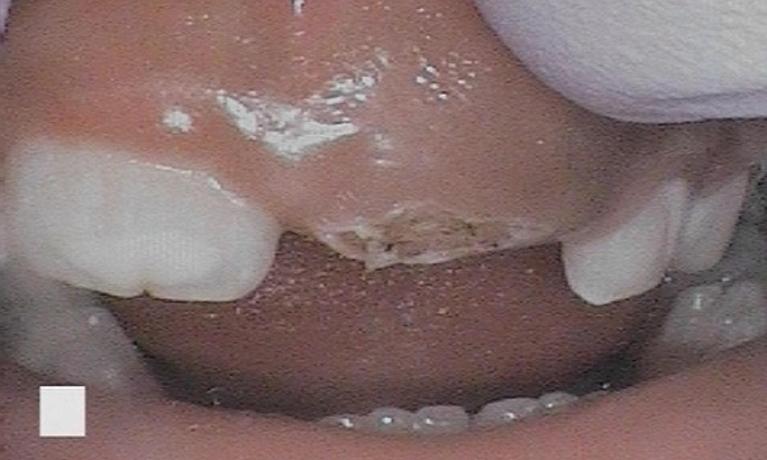

- Removing and filling cavities with minimal use of our dental drill and fewer numbing injections

- Destroying unwanted oral growths and relieving symptoms associated with cold sores and blisters